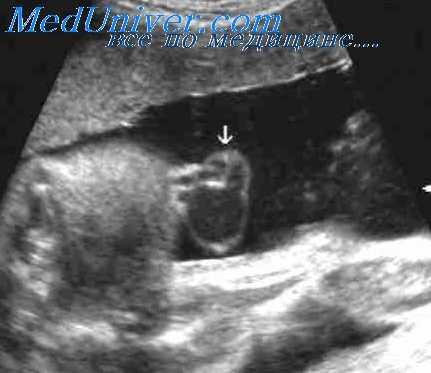

Омфалоцеле и гастрошизис отмечаются при аномалиях передней брюшной стенки плода. При омфалоцеле имеется срединно расположенный дефект пупочного кольца с выпячиванием через него в основание пуповины таких внутренних органов, как кишечник и печень. При ультразвуковом исследовании оно выглядит как образование, прилежащее к передней брюшной стенке плода и окруженное мембраной, к верхнему полюсу которого прикреплена пуповина.

При гастрошизисе наблюдается выпадение в окружающую амниотическую жидкость петель кишечника и других органов брюшной полости через дефект передней стенки, который локализуется в правой параумбиликальной области. Пуповина нормально прикрепляется слева от имеющегося дефекта, поэтому при эхографии гастрошизис имеет вид образования неоднородной структуры, которое располагается непосредственно рядом с областью прикрепления пупочного канатика.